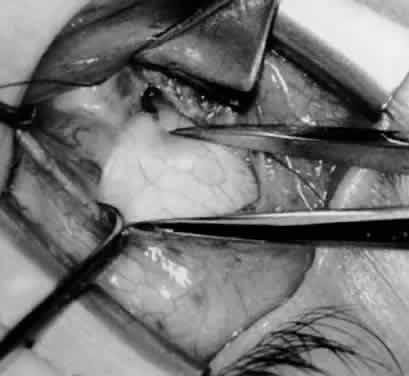

Fig. 11. Sutures are placed into the insertion of the inferior oblique muscle before it is sectioned from the globe for the recession procedure.

Fig. 12. An Aebli scissor is placed beneath the inferior oblique muscle insertion before it is sectioned from the globe.